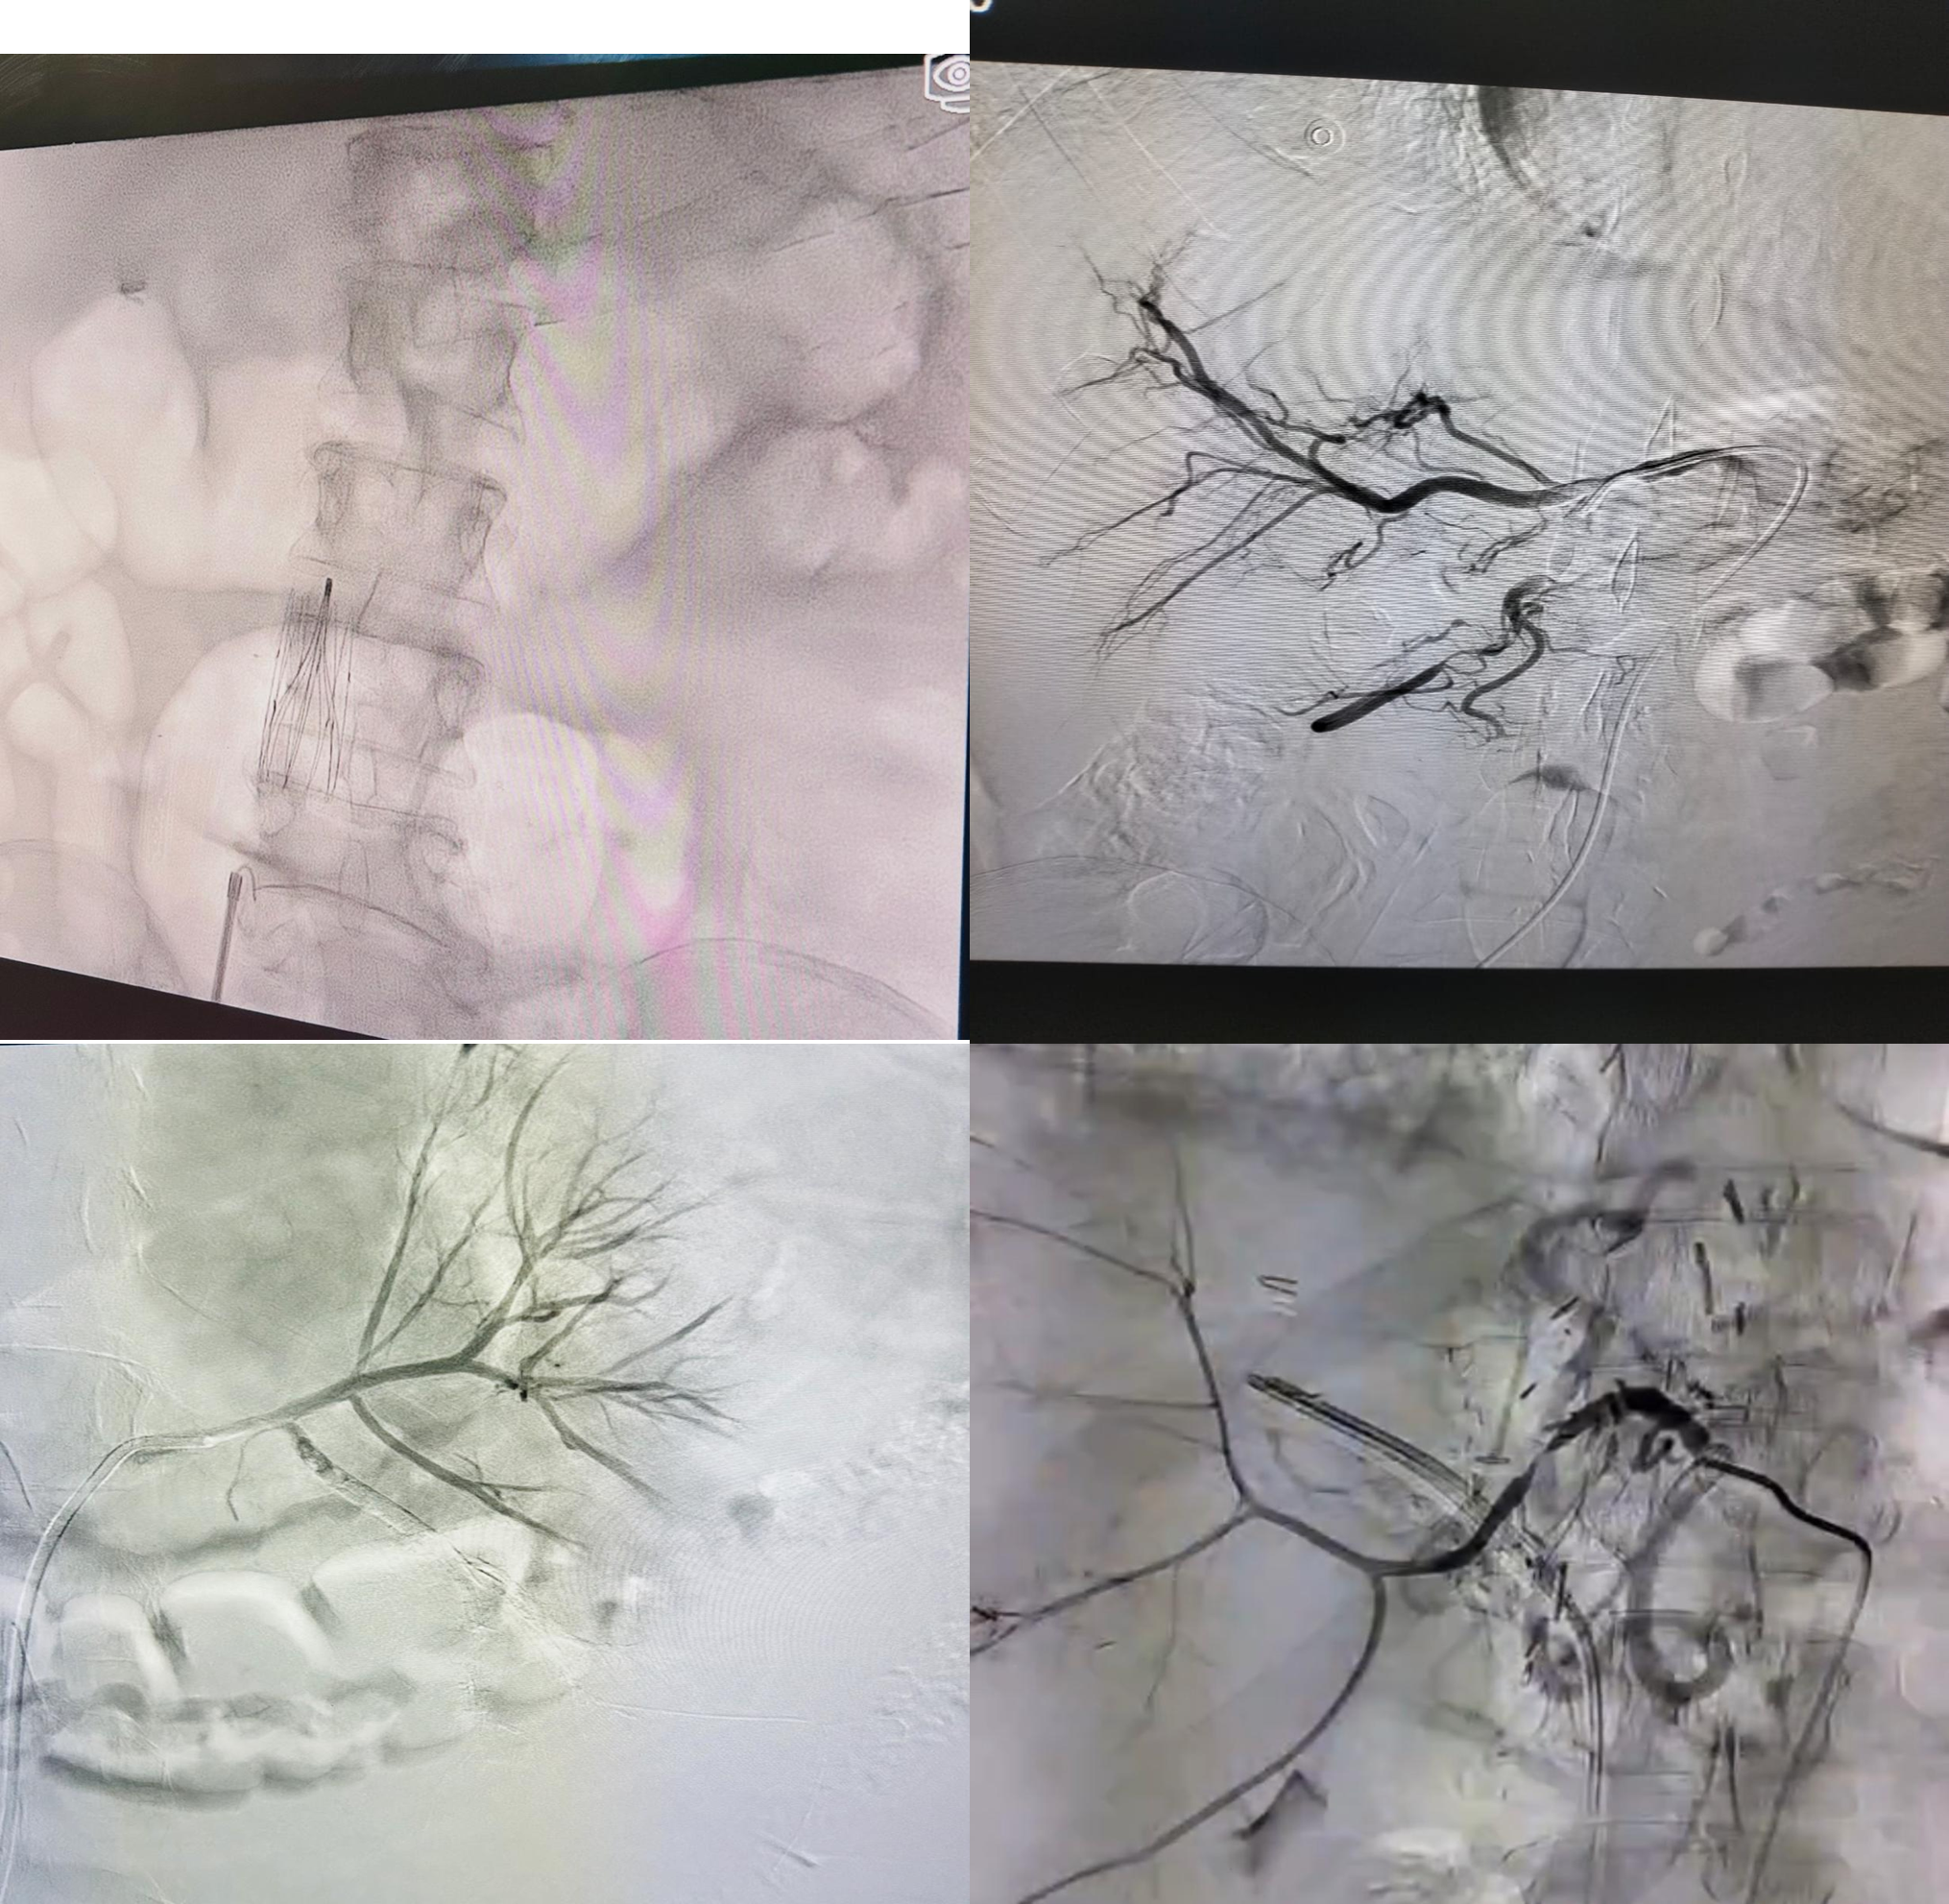

الأشعة التشخيصية والتداخلية والتصوير الطبي